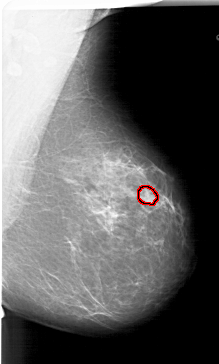

A_1767_1.LEFT_CC

LEFT_CC LINES 6496 PIXELS_PER_LINE 3781 BITS_PER_PIXEL 12 RESOLUTION 43.5 NON_OVERLAY

FILE: A_1767_1.RIGHT_CC.OVERLAY

TOTAL_ABNORMALITIES 1

ABNORMALITY 1

LESION_TYPE MASS SHAPE OVAL MARGINS CIRCUMSCRIBED

ASSESSMENT 3

SUBTLETY 3

PATHOLOGY BENIGN

TOTAL_OUTLINES 1

BOUNDARY